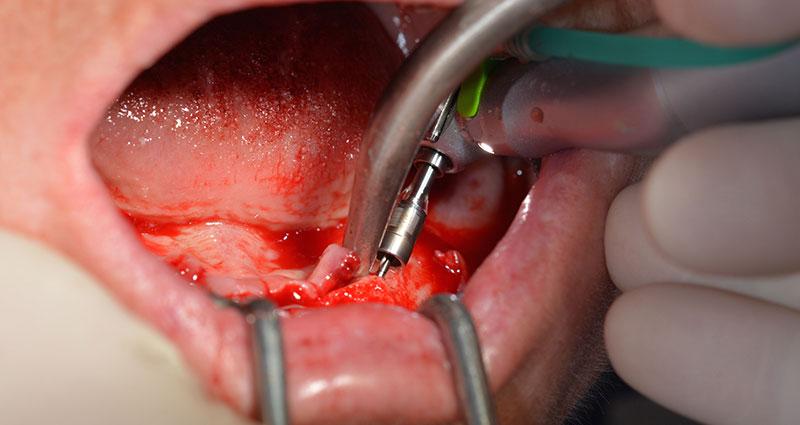

Tras la extracción de la dentición residual en el maxilar inferior, se realizó la incisión crestal en la región comprendida entre la pieza dental 37 y la 47.

A continuación, se identificó el agujero mentoniano (foramen mentale) como la estructura anatómica límite y se alisó el cortical de la cresta ósea con la pieza de mano recta y una fresa redonda grande (fig. 4).

Es en este momento, donde se hacen patentes las primeras ventajas de Implantmed. El protocolo quirúrgico ya está predefinido y guardado en distintas posiciones fijas que pueden seleccionarse con solo pisar el pedal en la posición «P» o desde la propia pantalla. En este caso, la pantalla iluminada también muestra en grande la velocidad de 35 000/rpm preajustada en la posición 1 (figs. 5 y 6).